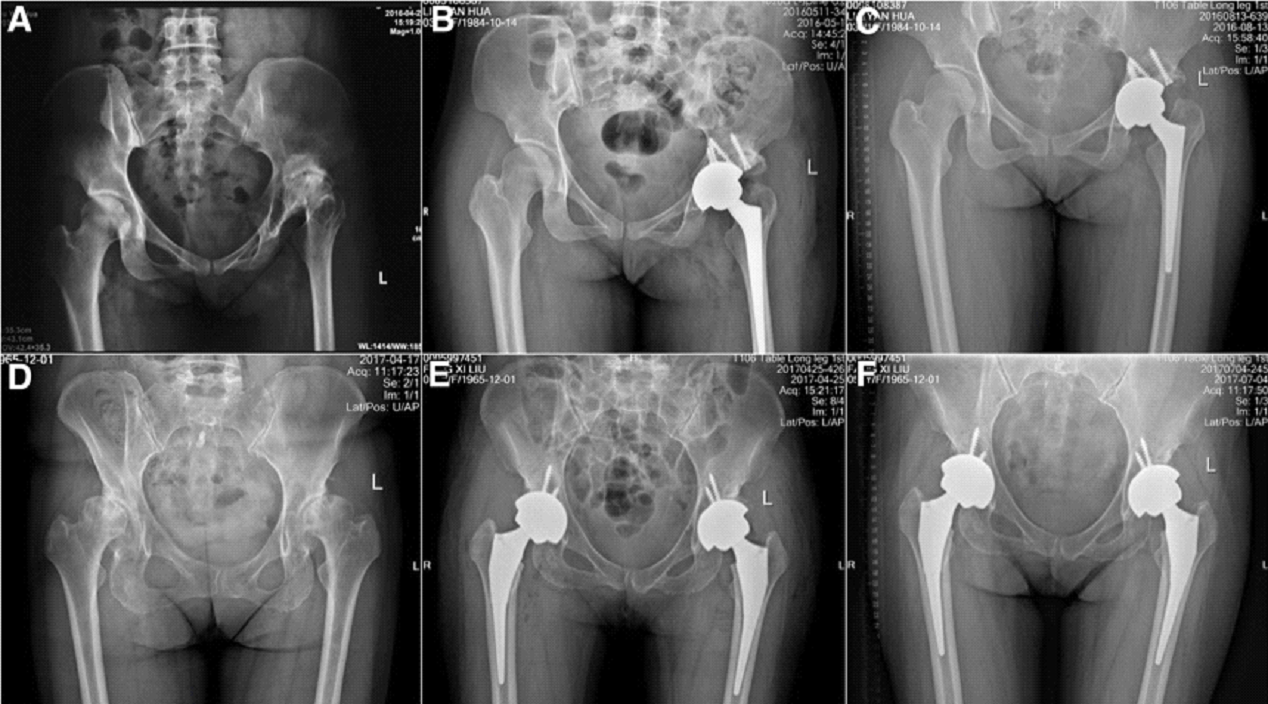

IN THR hip joint is replaced with metallic implant. Here both cup and ball is replaced

Similarly In TKR knee joint is replaced on both sides with metallic implant.in TKR both sides can be done together or done in staged manner one side at a time followed by other side